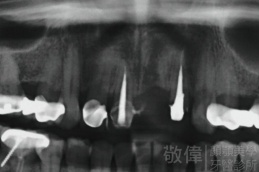

治療前-全口X光   治療後-全口X光